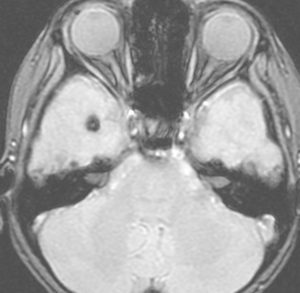

小児期の低線量照射で生じた多発性髄膜腫

5歳の時に白血病,化学療法と低線量頭蓋照射で治りました。ちゃんと就職して重機の運転をしていましたが,30歳,左足の痙攣で発症しました。多発性髄膜腫が発生していました。摘出する必要があるものです。グレード1の良性の髄膜腫です。